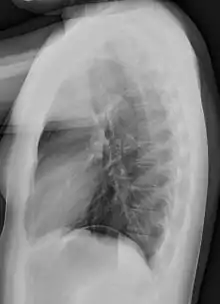

![]() A normal posteroanterior (PA) chest radiograph of someone without any signs of injury. Dx and Sin stand for "right" and "left" respectively. | |